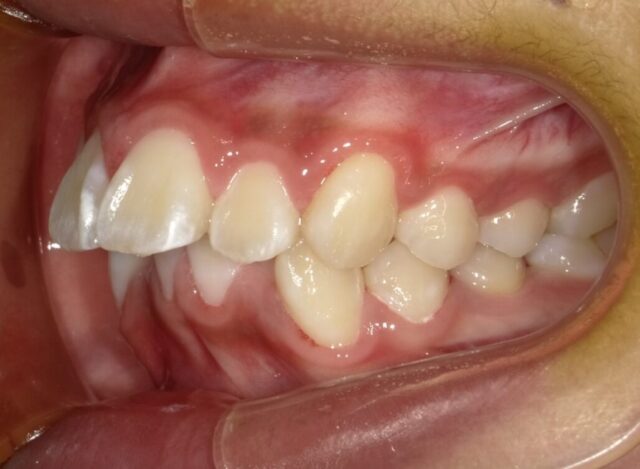

2024年6月(12歳8ヶ月)

永久歯揃いました。

本人のやる気がでたら

2段階目スタートします。